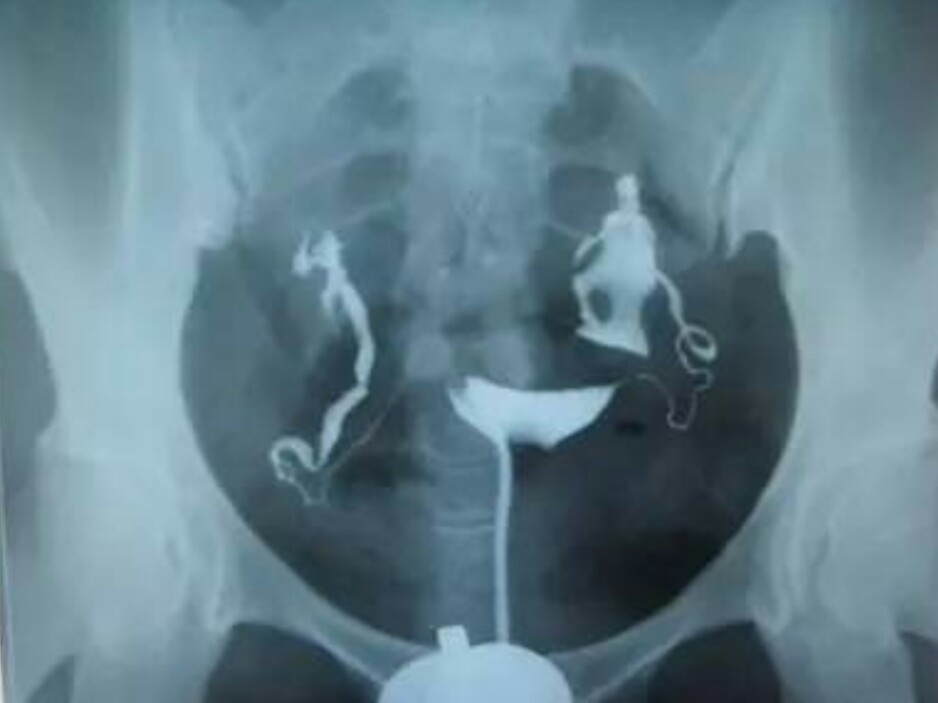

2.子宫输卵管X线碘油造影术——“有利有弊”

这是目前广泛使用的一种传统检查方法,可观察宫腔及输卵管腔情况,检查同时兼具疏通作用,方法是:从子宫颈管向子宫腔内注入碘剂,通过X线下显影,了解子宫及输卵管腔道内情况。该方法价格比较便宜,价值也得到肯定,但是对于远端微小粘连的判断不是很准确,而且放射线的辐射性可能有潜在危害,使用的含碘造影剂也有致敏可能。